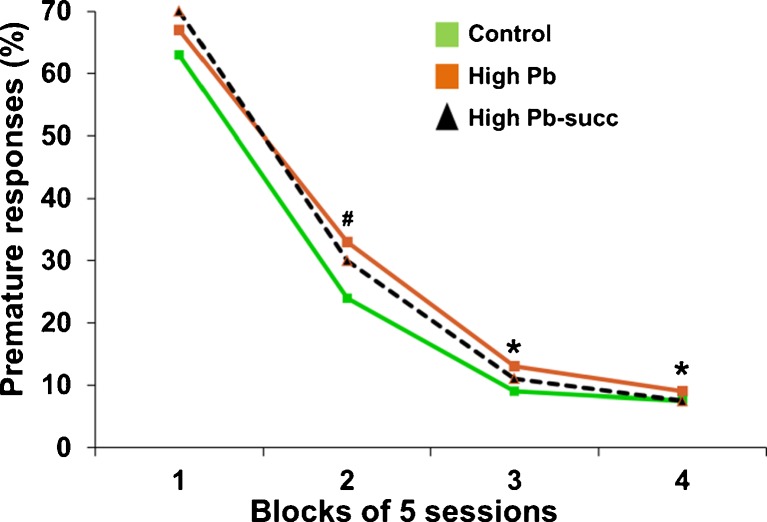

The results were a bit more complicated for the rats who received the higher lead exposure regimen (referred to as the high-Pb group in the tables and figures). These animals experienced a greater range of cognitive and affective dysfunction than those exposed to the lower lead exposure regimen, and the degree to which succimer was effective for these animals varied across these different functional domains, as summarized in Table 2. For example, the impaired learning of the high-Pb animals was in general not alleviated by succimer treatment; the high-Pb animals treated with succimer learned more slowly than the controls in the visual discrimination task and the attention task 1, and did not differ from their high-Pb-treated counterparts who had not been chelated. This pattern is depicted in Fig. 15, which illustrates the rate at which the animals learned to inhibit premature response in the first attention task that included long pre-cue delays on some trials. As seen in this figure, the high-Pb rats learned to wait for the cue more slowly than controls, and succimer chelation was only somewhat effective in normalizing learning rate (i.e., the succimer-chelated animals were not significantly different from controls or the high-Pb placebo-treated animals).

Fig. 15.

The impaired learning ability of the high-Pb rats was only somewhat alleviated by succimer chelation. Data show percent premature responses in attention task 1 as a function of the stage of testing (stages divided into blocks of sessions). Superscripts above symbols indicate level of significance for the contrasts between the high-Pb group and controls, #p < 0.07, *p < 0.05. Data from Stangle et al. [14]. [Reproduced with permission from Environmental Health Perspectives]